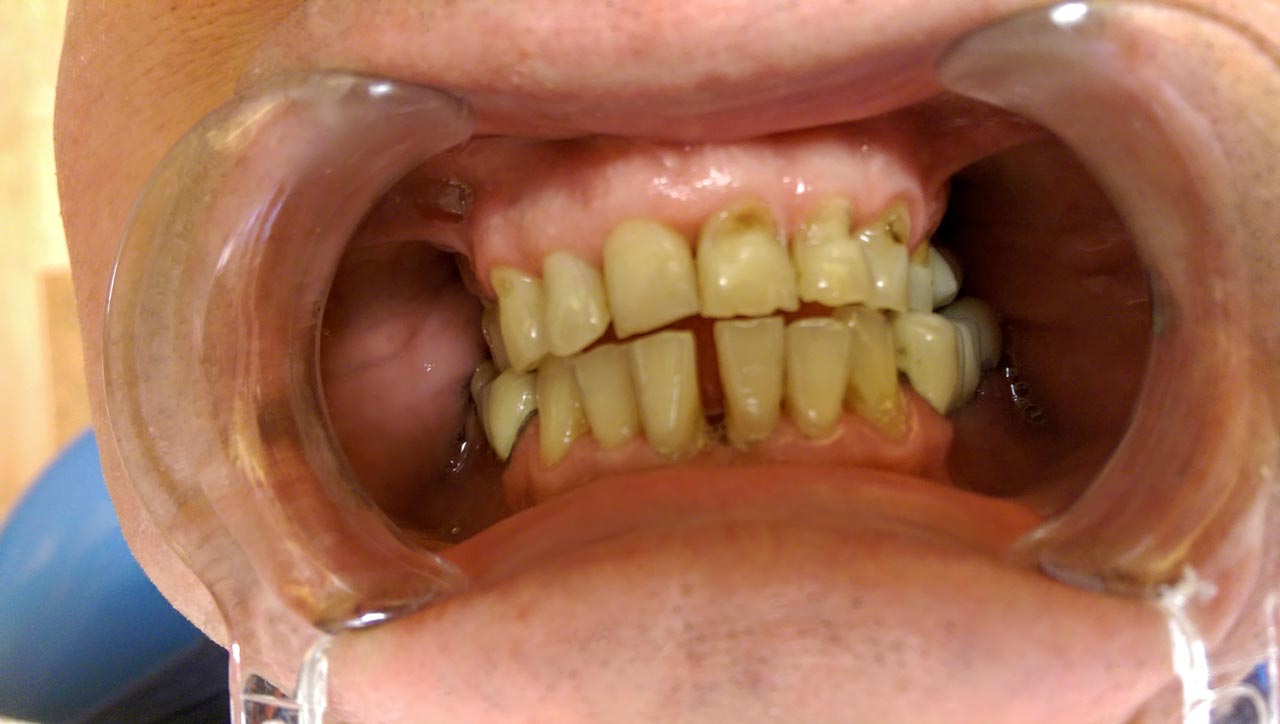

Teljes fogatlanság helyreállítása 2 nap alatt

Teljes fogatlanság helyreállítása 2 nap alatt azonnal terhelhető svájci IHDE implantátumokkal és PMMA műanyag hidakkal. Intraorális szkennerrel vettünk lenyomatot az implantáció után, és erre a digitális mintára készítette el a fogtechnika a hidak digitális tervezését, majd faragta ki műanyagból. Ezt a gyors munkát az azonnal terhelhető implantátumok és a digitális lenyomat, tervezés segítségével tudtuk megcsinálni mindössze 2 nap alatt. Dr. Kelemen Péter és a Symbion Fogtechnika munkája.